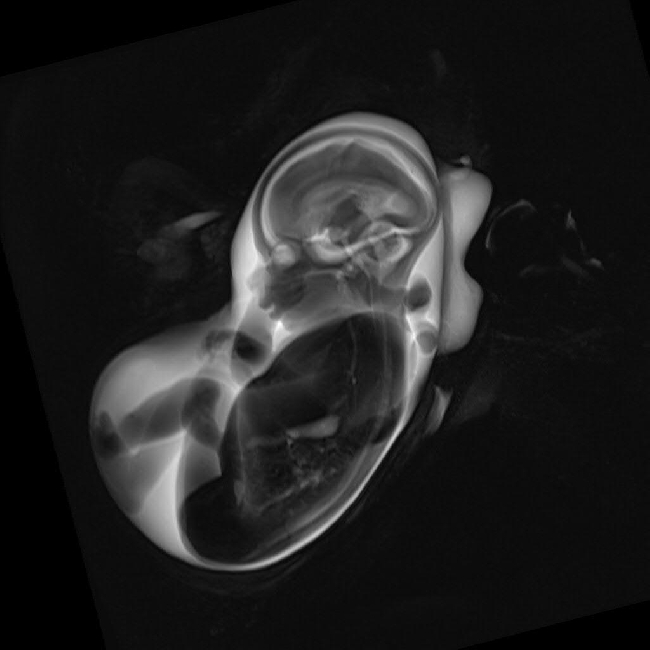

Prof. Mentzel:“ In Jena kann ich meine Vorstellungen umsetzen und die Kinderradiologie als gesamtes Gebiet der Bildgebung im Kindesalter von der fetalen MRT bis zur Bildgebung des Adoleszenten ausbauen. Der uneingeschränkte Zugang zu allen Modalitäten und die Untersuchung aller Organsysteme von der „Locke bis zur Socke“ machen Jena als Standort für die

Vor 3 Jahren haben wir die Radiologie mit Kinderradiologie als Wahltertial im Praktischen Jahr an der Universität Jena eingeführt. Über Vorlesungen, Praktika, Ultraschallkurse und Famulaturen gelingt es zunehmend besser, das vielen Studierenden früher unbekannte Fach Radiologie bekannt zu machen. Die Bemühungen um die „Köpfe“ sind vielfältig – aber auch alle anderen Fächer haben Nachwuchssorgen. Zur Attraktivität einer Ausbildungseinrichtung zählen heute neben der selbstverständlichen materiellen Ausstattung insbesondere fachliche Kompetenz, Respekt und Vertrauen. Am Universitätsklinikum in Jena habe ich sehr gute Forschungsbedingungen: ein Schwerpunkt liegt auf der prä- und postnatalen Entwicklung des ZNS sowie der urogenitalen Entwicklung und deren Störungen beim Feten und Neugeborenen.“

Zudem hat in Jena das Universitätsklinikum im Oktober 2012 eine extrem teure Besonderheit gekauft, die Jena auch künftig zu einem attraktiven Standort der Kinderradiologie macht und mit der man die Herausforderungen bei sehr kleinen Frühgeborenen noch besser meistern kann: Ein MR-tauglicher Inkubator einschließlich spezieller kleiner Spulen für die Untersuchung des Kopfes und des Körpers. Das Frühgeborene kann so auch während der MRT im Inkubator verbleiben, was es so nur in 3 Einrichtungen gibt.

Technische Neuheit in der Abteilung: der MR-taugliche Inkubator. Das Gerät ermöglicht die Erstellung von MRT-Aufnahmen, ohne dass das Frühchen aus dem Inkubator herausgehoben werden müsste.

Ein Frühchen im MR-Inkubator.

MRT-Aufnahme eines ungeborenen Kindes („fetales MR“)